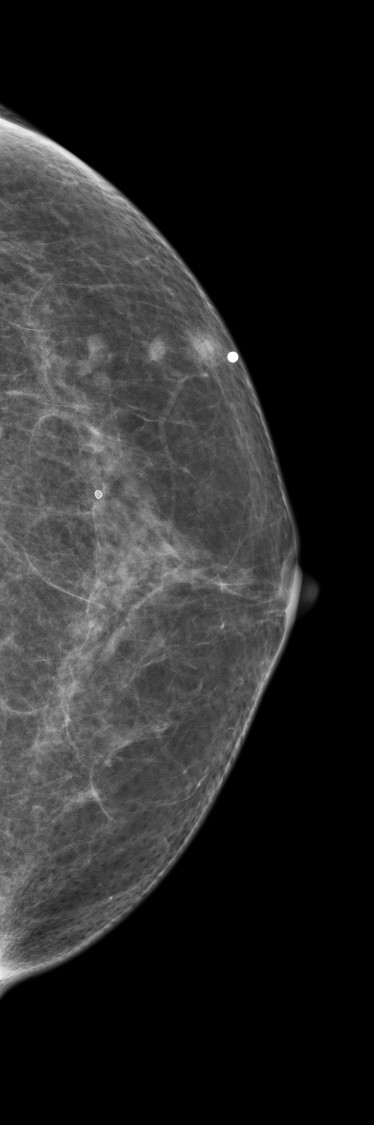

[355,Breast] 61/F,A palpable mass in the left breast

Breast

Modality

US,Etc,

What is your diagnosis?